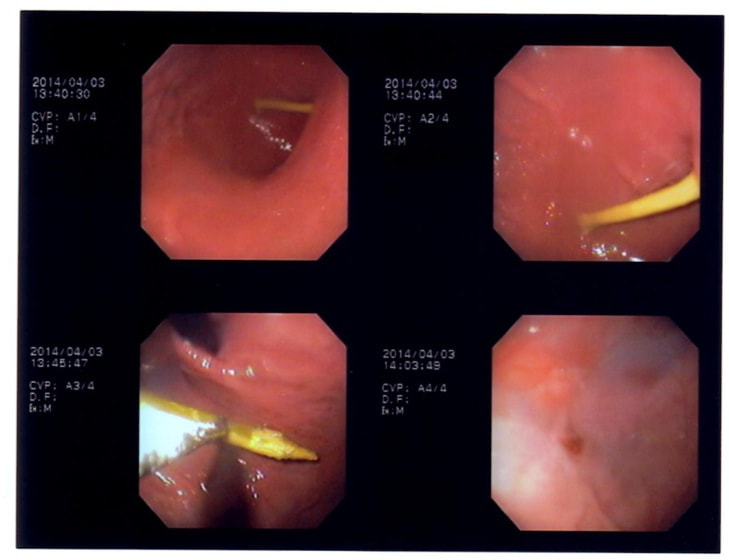

11歳 ミニチュア・ダックス 去勢オス

主訴:焼き鳥の竹串を食べたとの事で来院しました。元気・食欲は問題なく、嘔吐などの症状もありませんでした。便にも竹串が1/3程でているとの事でしたが、全ての竹串が出ていないため、内視鏡検査を実施致しました。

内視鏡検査所見:胃内に竹串の先端部分が残っていたため、異物鉗子にて摘出しました。胃内は、全体的に炎症を伴い、出血している部位も確認されました。摘出後は、胃粘膜保護薬・プロトンプインヒビター(胃薬)の内服2剤ならびに食事療法により経過は良好です。

摘出した竹串

内視鏡下写真

◎竹串誤飲は、異物の1位と言われるほど多く認められています。竹串は、先端が尖っているため消化管穿孔などを起こし、命に関わることもあります。万が一、ご自宅や散歩中に串などを食べてしまった場合は、病院まですぐご連絡下さい。また竹串は、食道を傷つけ・穴をあける恐れなどもあるため無理に吐かせる事は絶対にしないで下さい。本症例は、内視鏡下にて摘出が可能でしたが、状況によっては開腹が必要となる場合もあります。